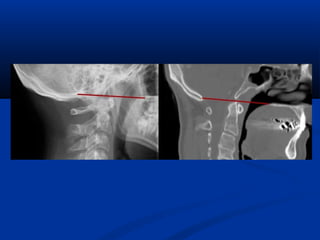

Sagittal CT images: right measures the basion-posterior axial line interval which is

denoted by the small horizontal red line.

The left image demonstrates measurement of the basion-dental interval which is

denoted by the vertical red line.

If either of these distances are greater than 12 mm then the diagnosis of

occipitocervical dissocation is fairly certain.